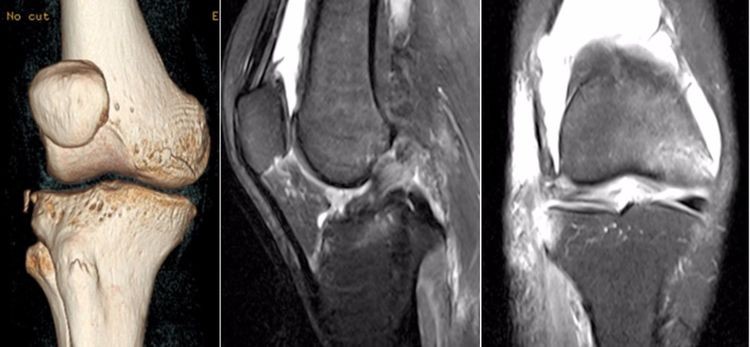

要提高ACL损伤MRI诊断的准确性,解剖永远是基础!同时,还需要充分了解ACL的受伤机制,针对性的阅片;MRI的矢状位、冠状位及轴位三者结合,以提高诊断的准确性与全面性!

2.jpg

ACL的正常MRI表现——

1.各序列均为低信号。

2.韧带平直,边界清楚,有较好的张力。

3.韧带内可有脂肪及滑膜条纹影。